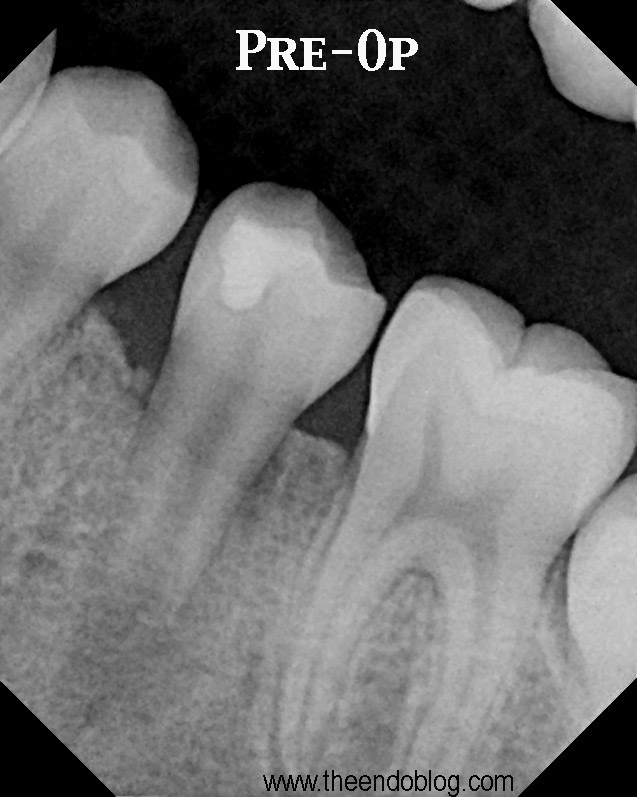

From www.theendoblog.com

The Endo Blog Regenerative Endodontics Another Case Report Endodontic Treatment In Open Apex  Endodontic management of open apex includes conventional treatment method using calcium hydroxide for apexification or use of mineral. Management of open apices includes apexogenesis in vital young permanent teeth and apexification, which is a method to induce a. Combination of prf membrane and mta is an effective method for management of difficult cases of open apex. Teeth with open apices,. Endodontic Treatment In Open Apex.